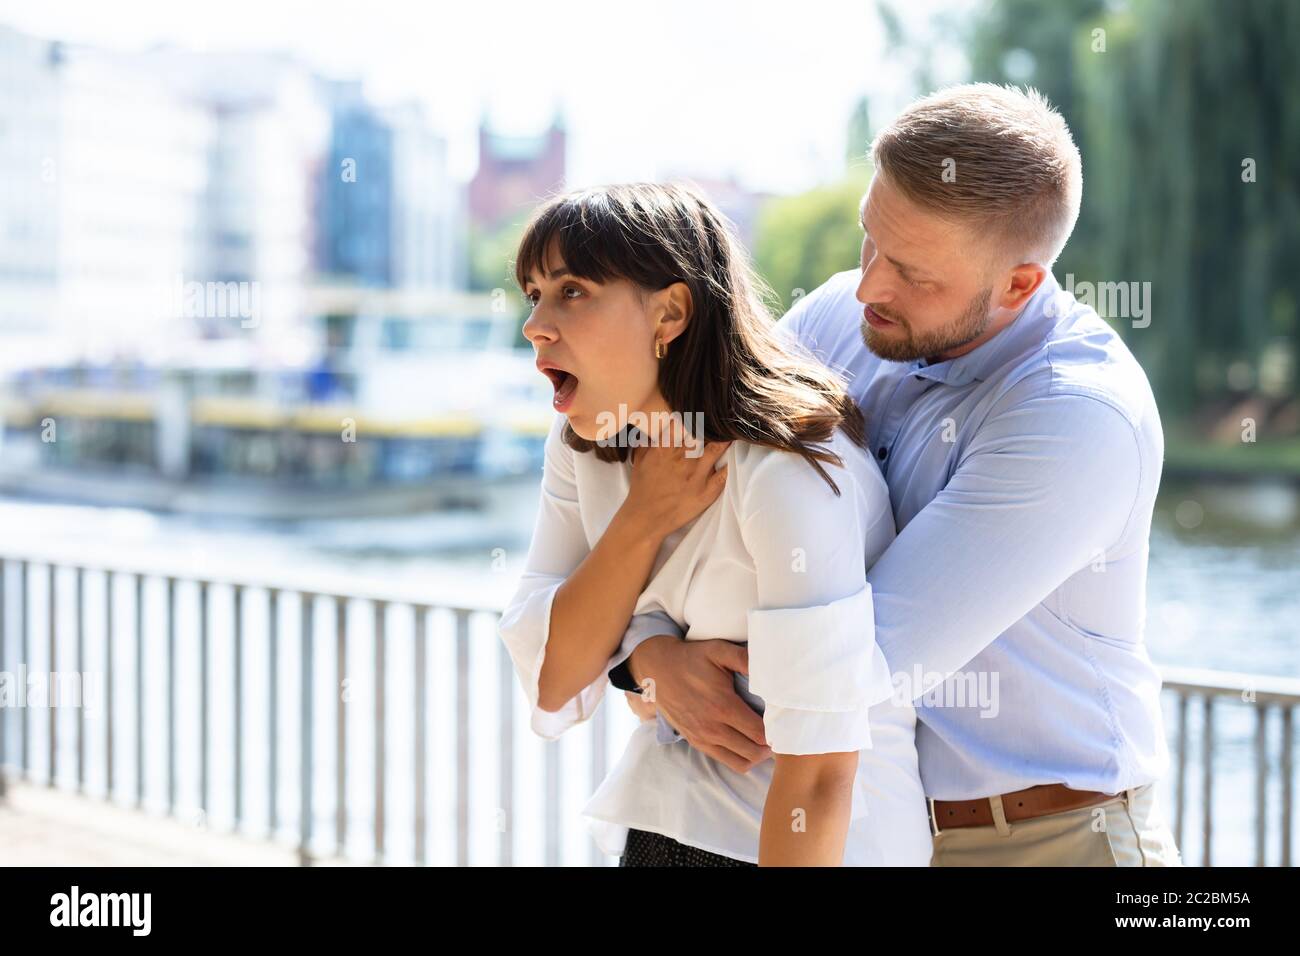

Man Helping Choking Woman To Expel A Trapped Object From Airway. Heimlich Maneuver Stock Photohttps://www.alamy.com/image-license-details/?v=1https://www.alamy.com/man-helping-choking-woman-to-expel-a-trapped-object-from-airway-heimlich-maneuver-image327215476.html

Man Helping Choking Woman To Expel A Trapped Object From Airway. Heimlich Maneuver Stock Photohttps://www.alamy.com/image-license-details/?v=1https://www.alamy.com/man-helping-choking-woman-to-expel-a-trapped-object-from-airway-heimlich-maneuver-image327215476.htmlRF2A09XK0–Man Helping Choking Woman To Expel A Trapped Object From Airway. Heimlich Maneuver

Man Helping Choking Woman To Expel A Trapped Object From Airway. Heimlich Maneuver Stock Photohttps://www.alamy.com/image-license-details/?v=1https://www.alamy.com/man-helping-choking-woman-to-expel-a-trapped-object-from-airway-heimlich-maneuver-image362904342.html

Man Helping Choking Woman To Expel A Trapped Object From Airway. Heimlich Maneuver Stock Photohttps://www.alamy.com/image-license-details/?v=1https://www.alamy.com/man-helping-choking-woman-to-expel-a-trapped-object-from-airway-heimlich-maneuver-image362904342.htmlRF2C2BM5A–Man Helping Choking Woman To Expel A Trapped Object From Airway. Heimlich Maneuver

Man Helping Choking Woman To Expel A Trapped Object From Airway. Heimlich Maneuver Stock Photohttps://www.alamy.com/image-license-details/?v=1https://www.alamy.com/man-helping-choking-woman-to-expel-a-trapped-object-from-airway-heimlich-maneuver-image362904343.html

Man Helping Choking Woman To Expel A Trapped Object From Airway. Heimlich Maneuver Stock Photohttps://www.alamy.com/image-license-details/?v=1https://www.alamy.com/man-helping-choking-woman-to-expel-a-trapped-object-from-airway-heimlich-maneuver-image362904343.htmlRF2C2BM5B–Man Helping Choking Woman To Expel A Trapped Object From Airway. Heimlich Maneuver